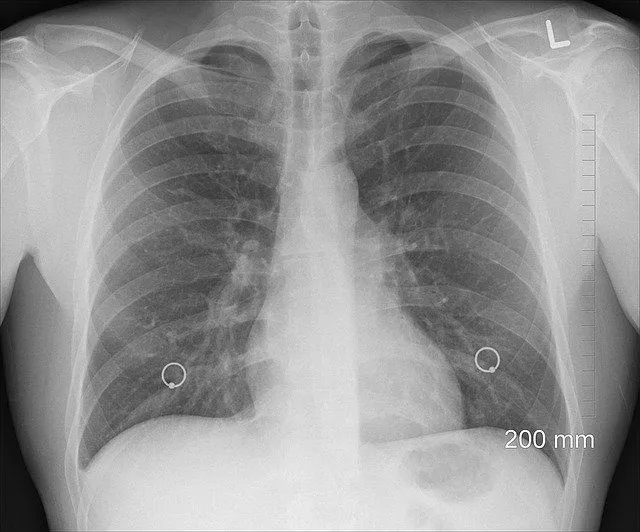

Восстановятся ли легкие после короны?

Радио Sputnik взял интервью у пульмонолога Александра Карабиненко, который рассказал, какова вероятность полного восстановления легких после перенесенного коронавируса.

По мнению врача, легкие человека, переболевшего ковидом, регенерируются самостоятельно. Как долго это будет происходить – три месяца или год – зависит от иммунитета. Однако Карабиненко отметил, что в том случае, если человек курит, о полном восстановлении жизненно важного органа речи не идет: курильщик медленно убивает себя, не позволяя легким регенерироваться.

Врач подчеркнул, что в период, пока легкие восстанавливаются, у человека может присутствовать кашель или одышка. Это объясняется фиброзными изменениями органа.